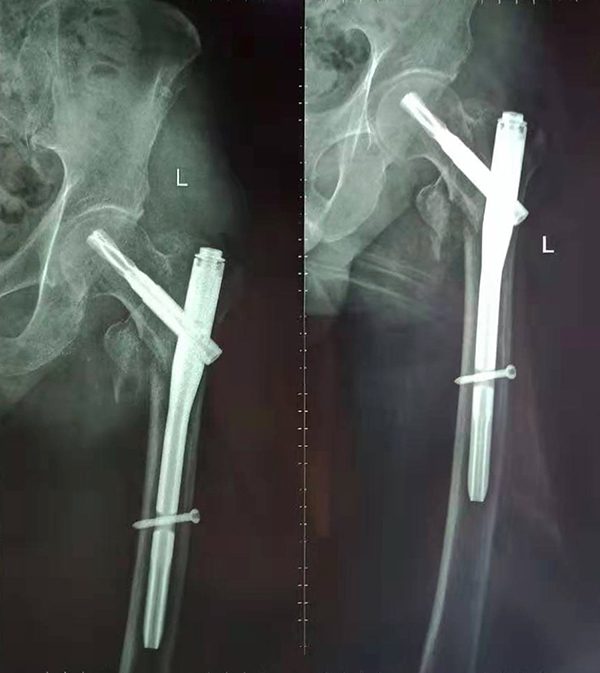

經(jīng)術(shù)前仔細(xì)的檢查和評(píng)估,與張爺爺家屬充分溝通,決定了實(shí)施閉合復(fù)位PFNA內(nèi)固定術(shù)的方案,劉鴻程主任說到,該術(shù)式的創(chuàng)傷小、出血少,適合骨質(zhì)疏松病人,術(shù)后解除患者疼痛,可以早期開始活動(dòng),便于護(hù)理。

手術(shù)后

9月10日上午,骨科順利完成張爺爺?shù)淖蠊晒谴致¢g骨折髓內(nèi)釘內(nèi)固定術(shù)。手術(shù)過程中麻醉平穩(wěn),術(shù)中出血量少,骨折手術(shù)時(shí)間持續(xù)一個(gè)多小時(shí)。